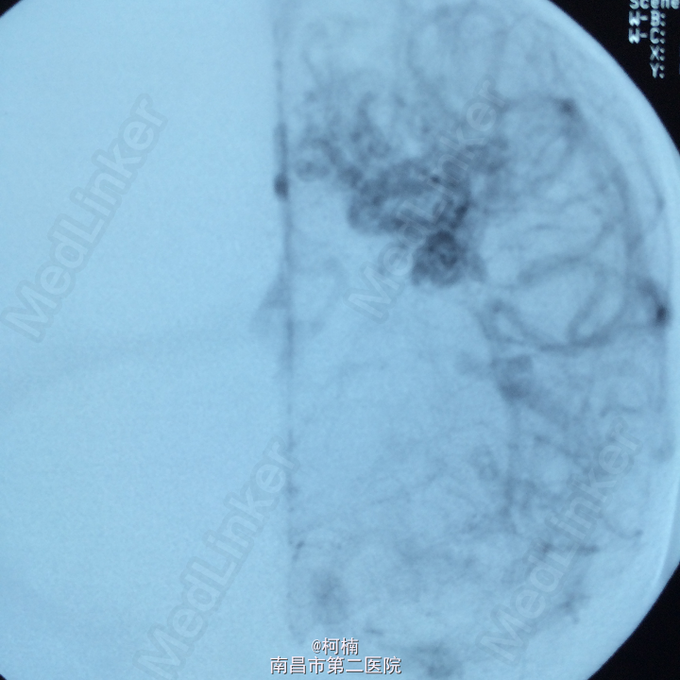

诊断:脑动静脉畸形 处理:予急诊行DSA检查,提示脑动静脉畸形,予行血管内栓栓塞治疗